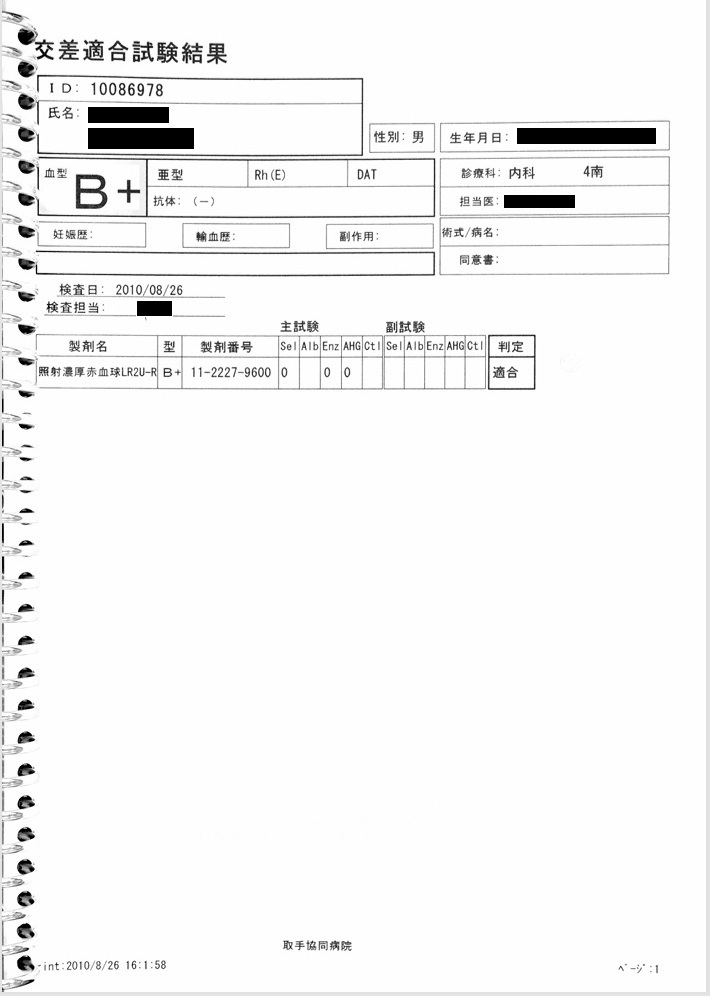

- 8月26日:Hb 11.1 g/dlで輸血開始

貧血にて輸血開始(カルテ・看護記録に記載あり)。しかし当日の血液検査ではHb 11.1 g/dlと貧血は軽度。 Hb 11.1 g/dlが本当であれば不適切診療。輸血が必要な状態であれば、Hb 11.1 g/dlは虚偽。

証拠:カルテ・看護記録・血液検査の抜粋